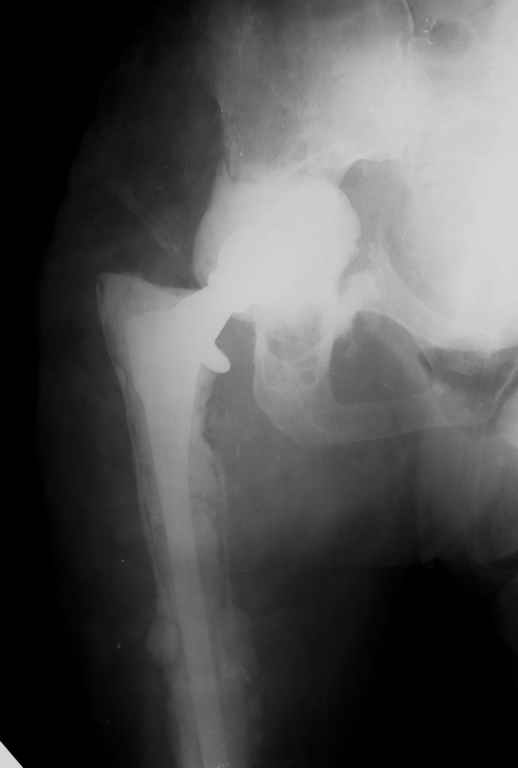

Апрель 2005 |  Декабрь 2005 |  Декабрь 2005 | Реревизия по поводу нестабильности вертлужногокомпонента была выполнена в апреле 2005 г. с пересадкой вертлужной впадины (аллотрансплантат)и защитой трансплантата кольцом Б-Ш.Нагноение выявлено через 6 месяцев, был полностью удален эндопротез (и вертлужный и бедренный компоненты), тщательная ХО мягких тканей с установкой подготовленной из цемента с антибиотиками (родной гентамицин + насыпной ванкомицин) вертлужной впадины опять же на цемент. Установлена новая ножка взамен удаленной на к/цемет с антибиотиками. Рана зажила, б-ая выписана домой. По этой методике прооперировано четверо б-х, пока без рецидива инфекции, одна из пациенток уже поступила для второго этапа.С уважением, Р.Тихилов

Большое спасибо за снимок, теперь все видно! Кстати, по этому поводу: в зоне бедренной кости кортикала осталось очень мало. Планируете ли Вы при окончательной имплантации менять эту ножку на другую (и если да, то на какую именно)?